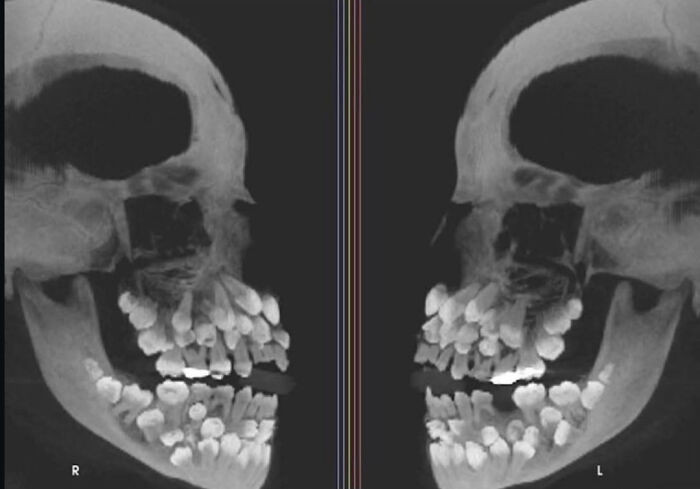

X-ray showing hyperdontia, extra teeth, and unnaturally expanded dental structure.reddit.com

An X-ray of a patient with hyperdontia, a condition where a person has more teeth than normal. Most adults have 32 teeth, but this individual had 81.